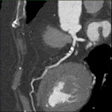

Automated contrast evens attenuation across weight ranges